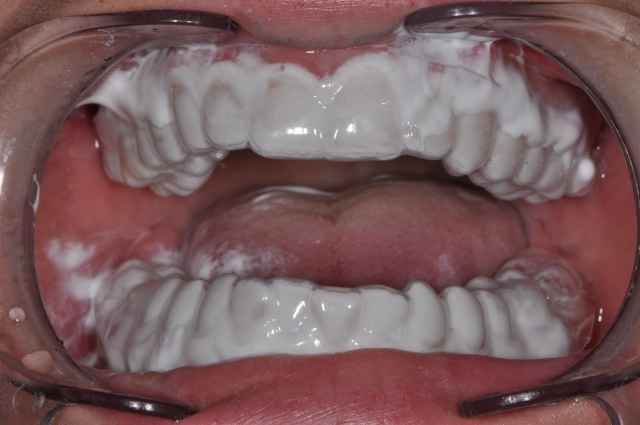

- Apply the paste in premade trays (I use standard bleach or fluoride delivery trays made at the consultation appointment).

- After application for 5 minutes, the patient can expectorate the material but should not rinse. The material will dissolve.